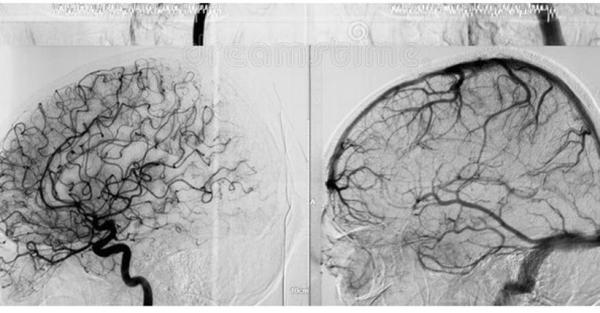

Gambaran metode cuci otak atau dalam dunia medis dikenal sebagai DSA yang dikembangkan dr Terawan Agus Putranto Sp Rad (K). (Foto: Ist).

Gambaran metode DSA. (Foto: Ist)

Menurut Terawan, metode modifikasi DSA ini dimulai dengan pemeriksaan detail terhadap pasien menggunakan diagnostik yang paling canggih lalu dilakukan check-up dahulu. Pengecekan otak dimulai dengan MRI lalu neurologis melalui peralatan yang tersedia di RSPAD.

Setelah ditemukan sesuatu, dia akan memutuskan tindakan apa yang harus dilakukan. ”Apakah harus melakukan DSA untuk menentukan diagnostik sekaligus melakukan tindakan lanjutannya,” kata dia.

Setelah itu, menurut Terawan, timnya akan melakukan modifikasi dalam DSA sehingga keamanan pada pasien terjamin dan keadaan pasien jauh lebih baik karena didiagnosis dengan tepat.